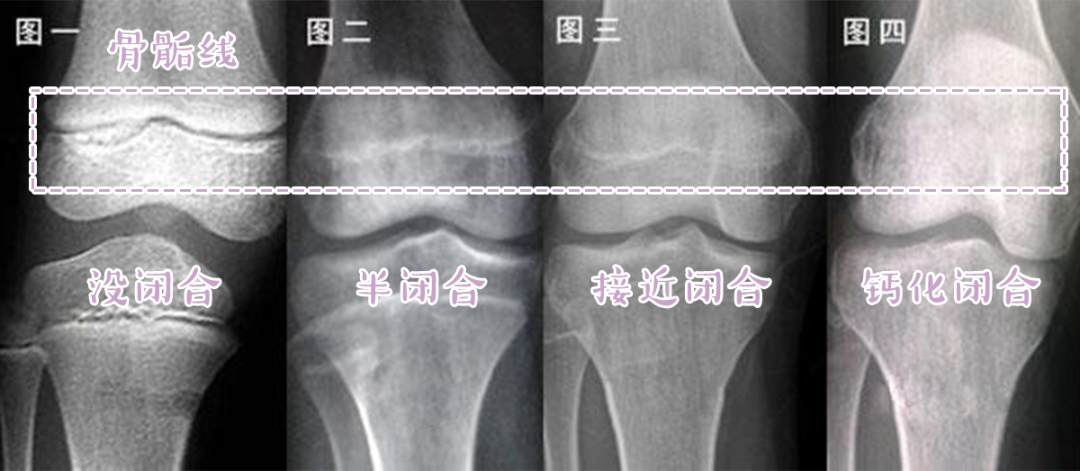

骨骺线闭没闭合对比图

骨骺线是骨骺与干骺端之间的软骨,它在x光片上表现为一条较宽的透光带

骨骺线闭合」也就是常说的这个结果我们就会停止生长等骺板彻底骨化后